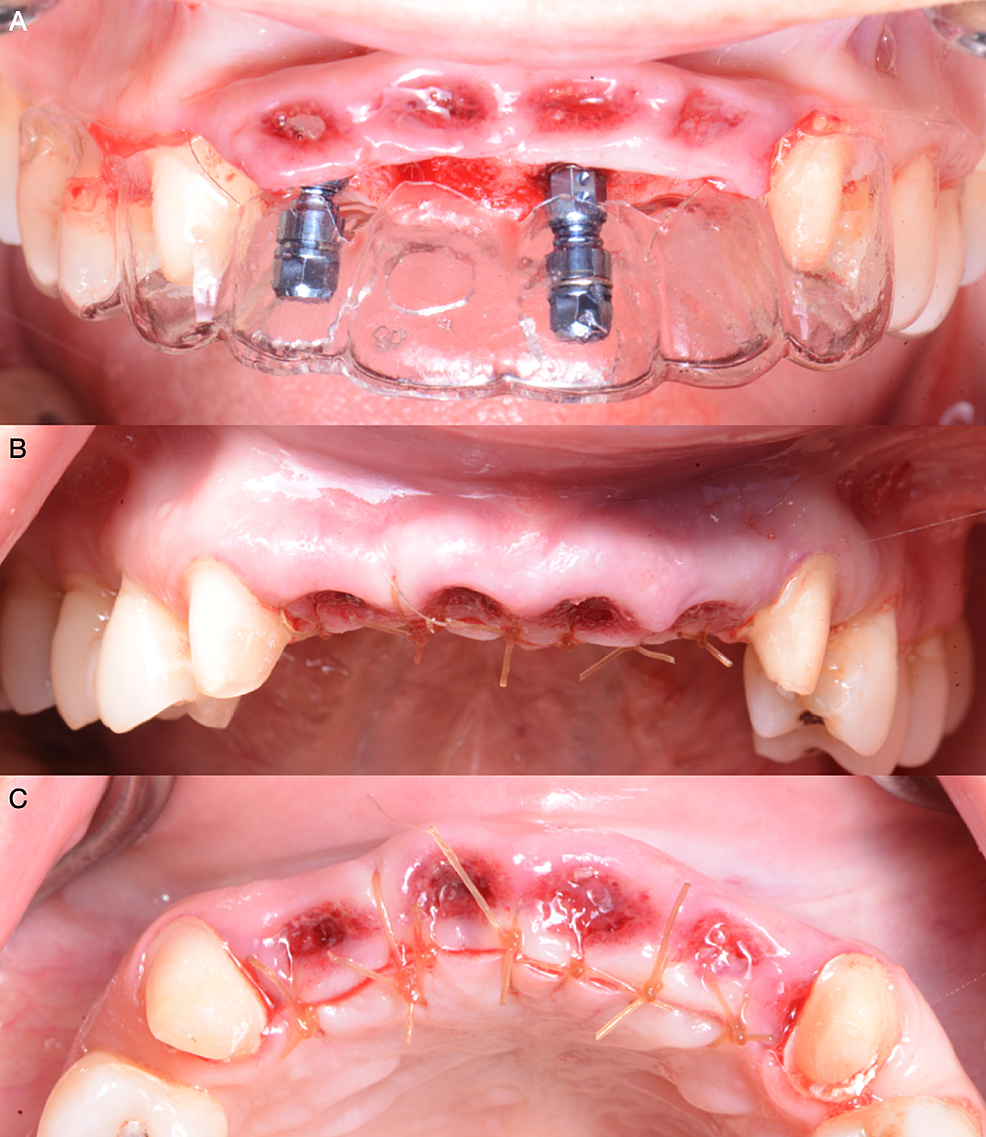

The implant was planned using implant software after the soft tissue’s desired shape was achieved (SimPlant, Dentsply Sirona Implants Inc, York, PA, USA) (Figure 6). Two implants at the maxillary right lateral incisor and maxillary left central incisor sites were planned to support a dental prosthesis from the maxillary left lateral incisor to the right lateral incisor. These sites were chosen based on the condition and thickness of the bone in the incisor region. Two weeks after the soft tissue contoured, the implant surgery was performed with a palatally-oriented crestal incision and bilateral sulcular incisions on the canines to reflect a full mucoperiosteal flap. The incision lines for the surgical flap were placed to avoid damaging the soft tissue line created during the preparation. Two bone-level implants of size 4.1mm (BLT RC, Straumann Group, Basel, Switzerland) were inserted (Figure 7A). For primary soft tissue closure, a simple interrupted suture technique (Polysyn FA, Surgical Specialties Corporation, Wyomissing, PA, USA) was used (Figure 7B, 7C). The implants were not loaded, and the existing fixed provisional restoration was cemented back onto the canines. During the two months of osseointegration, the provisional restorations maintained the soft tissue architecture that had been previously obtained.